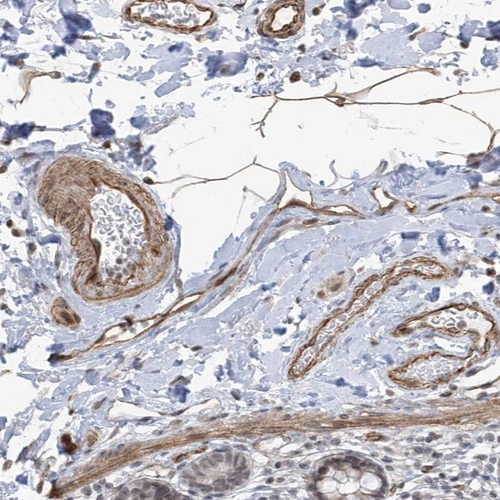

Immunohistochemical staining of human smooth muscle shows cytoplasmic positivity in smooth muscle cells.